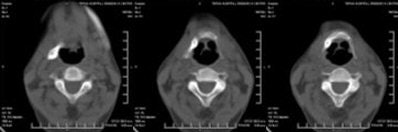

CT scan showed the presence of ossification of the right stylohyoid chain articulating with the hyoid bone. An elongated styloid process was present on the left side.